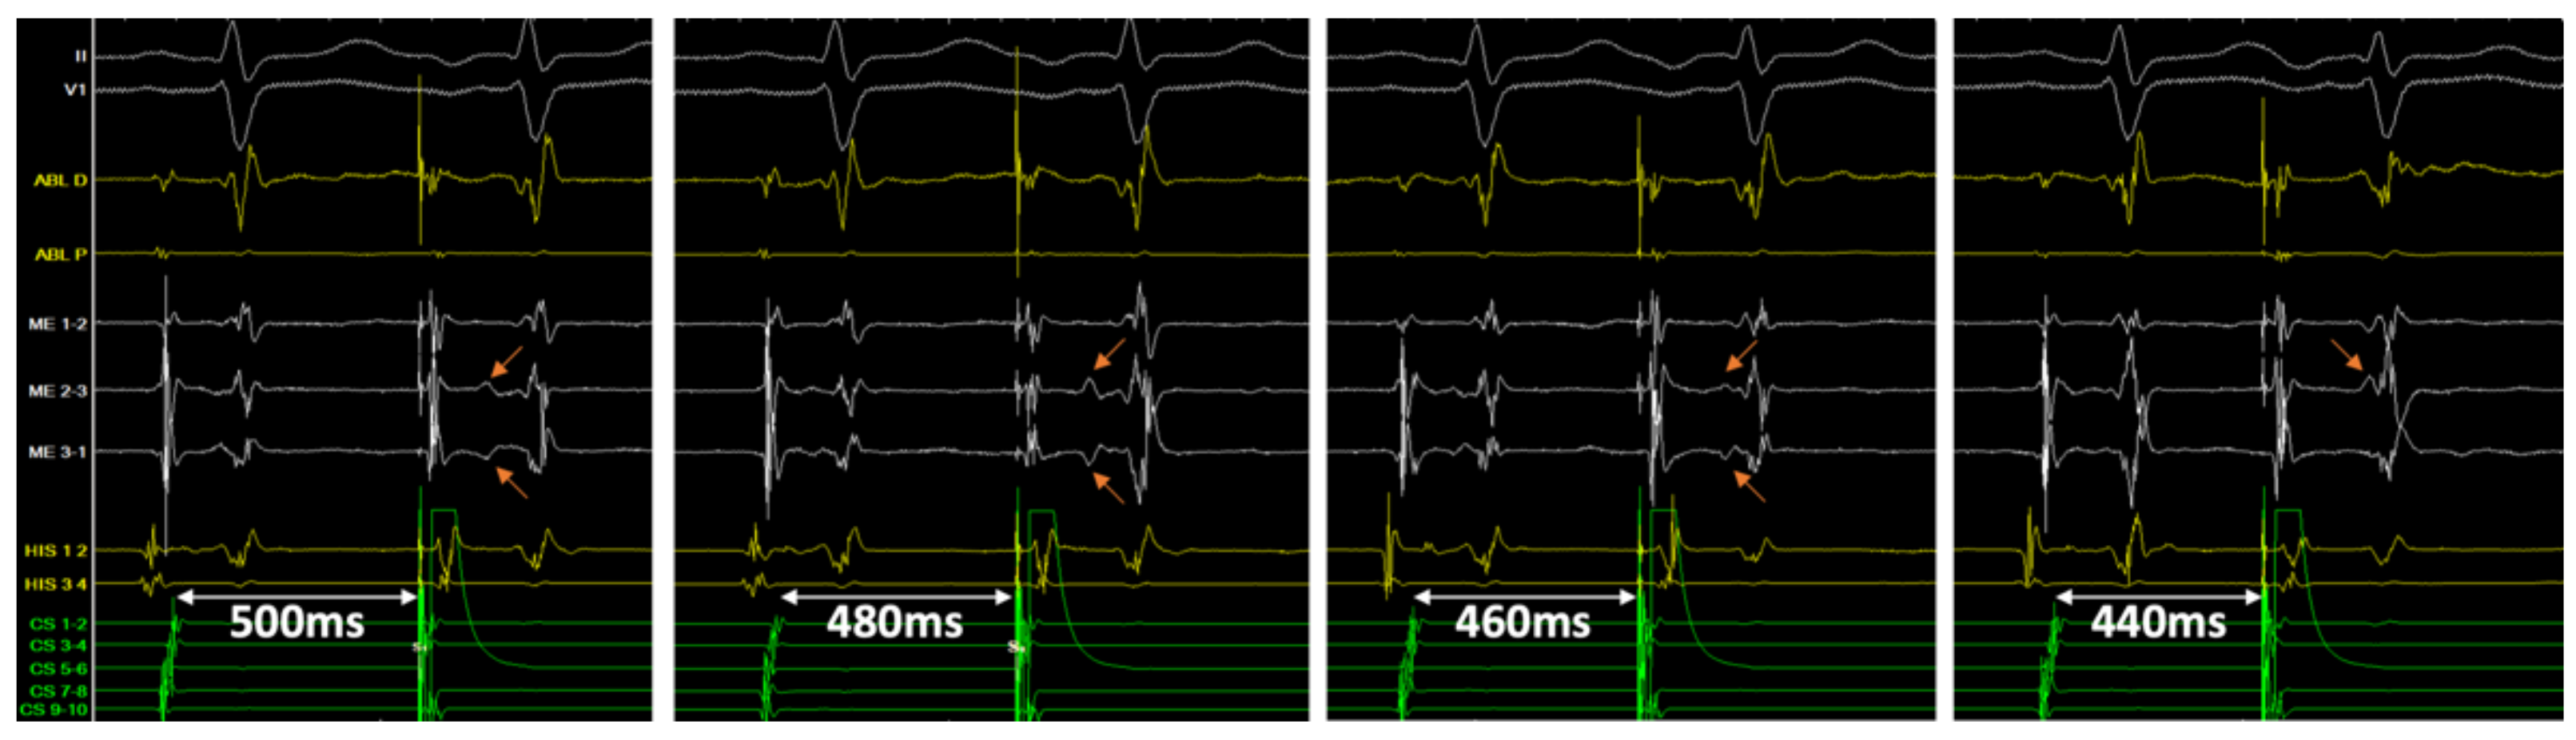

3.5. Double Potentials